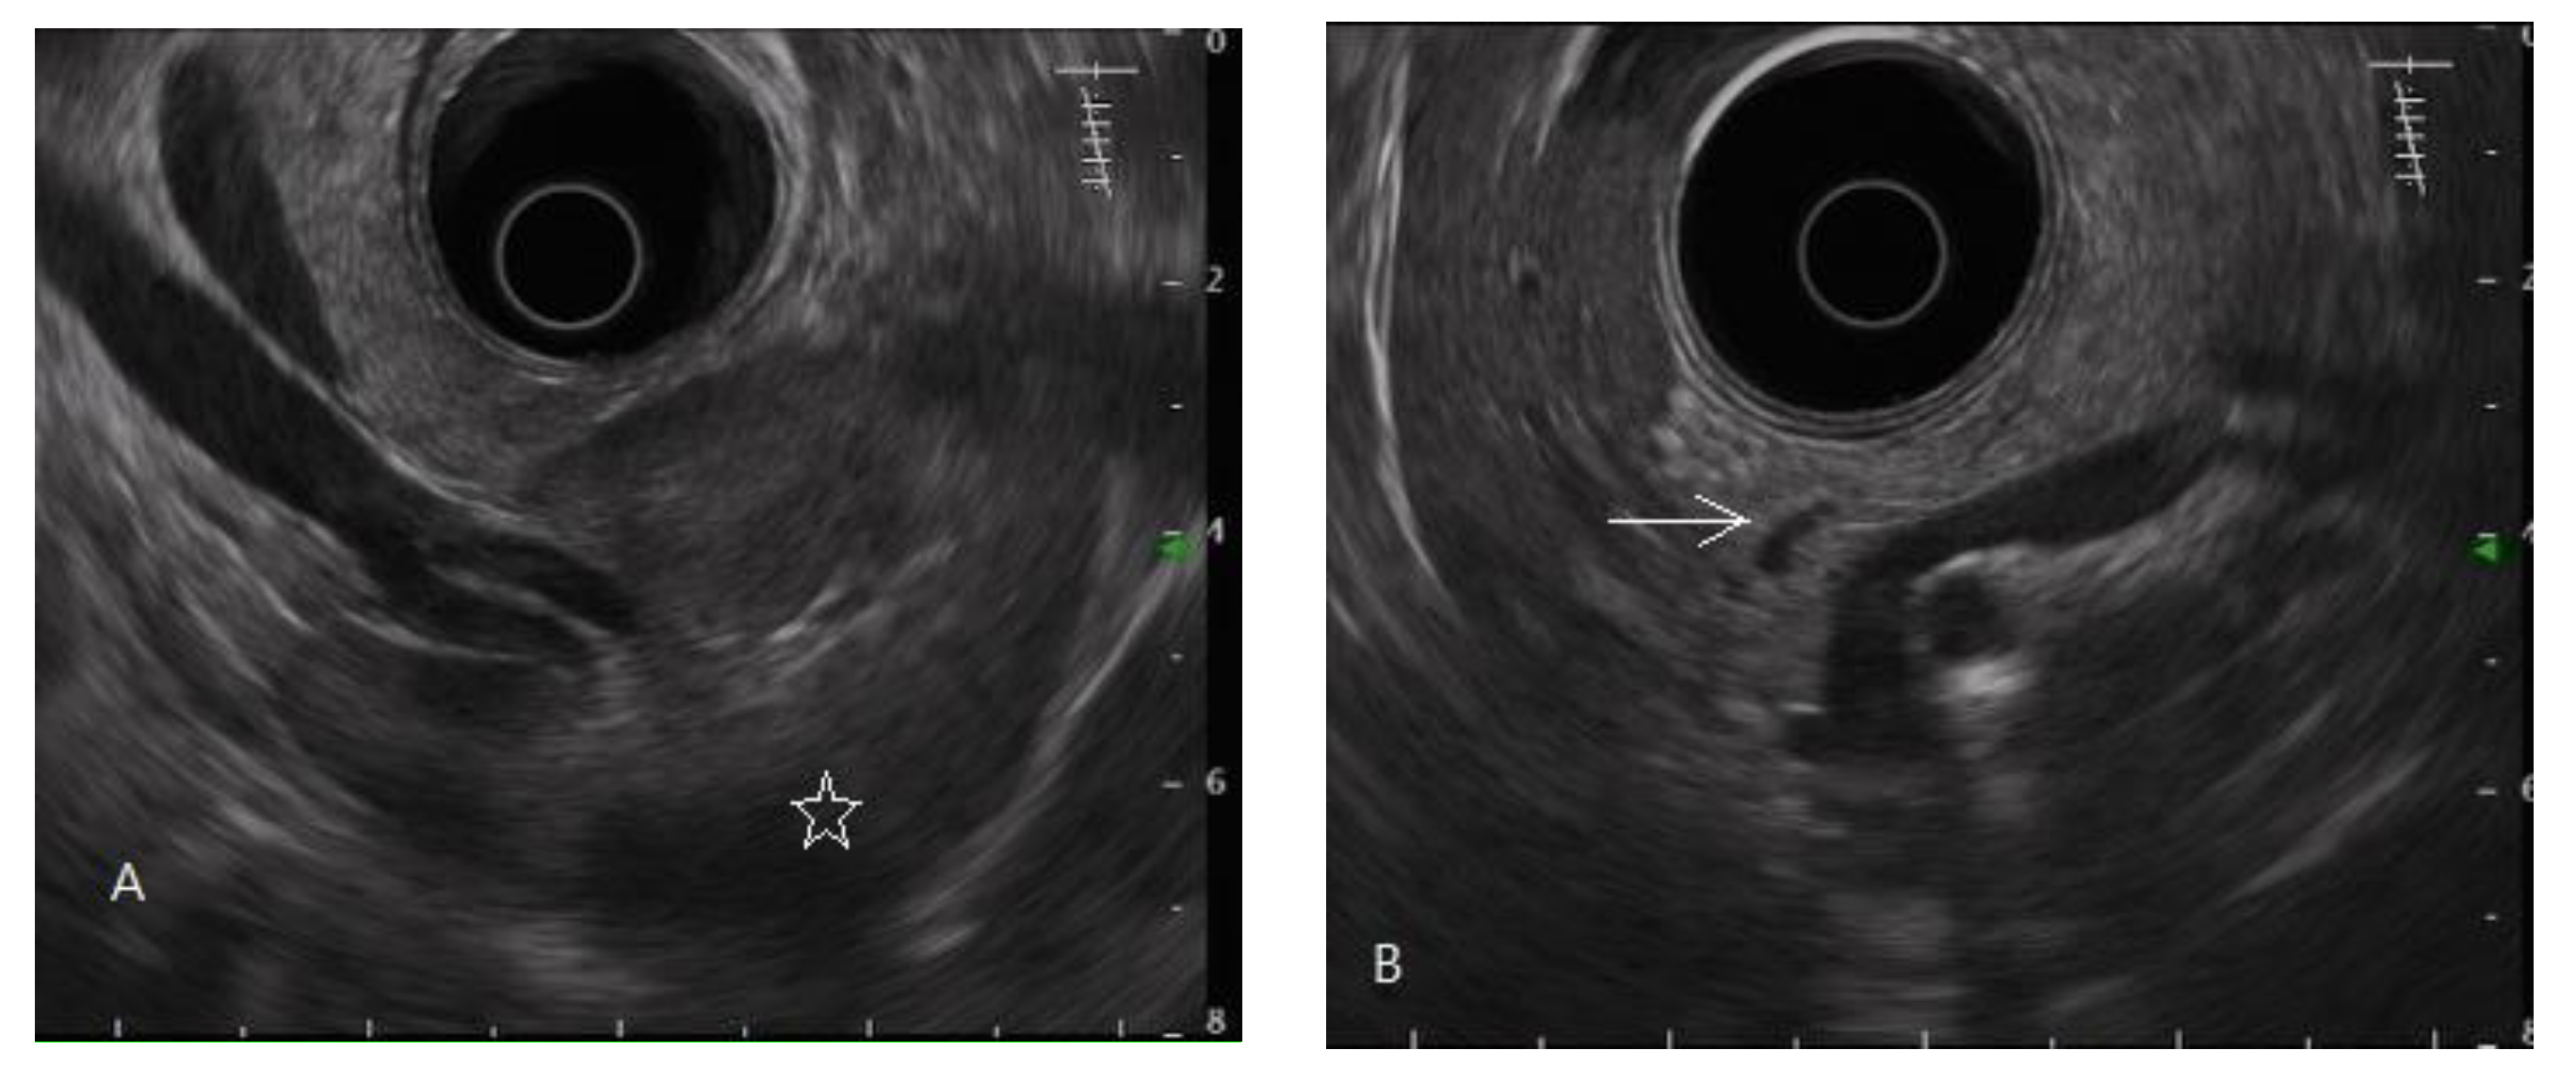

Figure 1.

Endoscopic ultrasonography of a normal pancreas. The normal pancreatic parenchyma is homogeneous, and the main pancreatic duct edge is non-hyperechoic. (A) Pancreatic tail, body; spleen (star mark), splenic vessels. (B) Pancreatic body, neck, partial main pancreatic duct (arrow mark). (C) Pancreatic head, uncinate process (hypoechoic ventral part, arrow mark); gallbladder; partial main pancreatic duct. (D) Pancreatic head; gallbladder (star mark); main pancreatic duct (arrow mark).